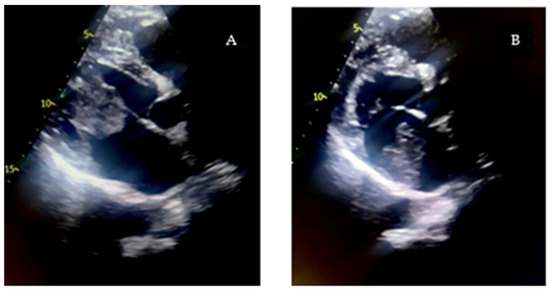

The excised mass was submitted for histopathological examination, which confirmed the diagnosis of cardiac myxoma.

Histopathological examination confirmed the diagnosis of cardiac myxoma, showing tumor cells arranged in nests and cords within a myxoid stroma, with fibrino-hematic deposits on the surface (Figure 4 and Figure 5).

Figure 4. Intra-atrial myxoma—tumor cells arranged in a myxoid stroma, fibrino-hematic deposit on the tumor surface. HEx100.